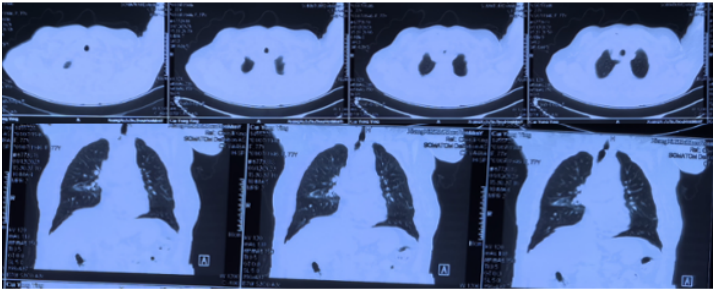

12月8日复查胸部CT,气管管径较前明显增宽(图10)。患者于12月14日出院,于当地定期复查。病例3:80岁,男性,发现颈部肿块5年,咳嗽气促1个月入院(2024年1月6日)。2019年1月14日曾于外院置入气管硅酮支架。术前(1月6日):HR 95次/min,R 22次/min,静息下SpO2 97%(FiO2 29%),活动后喘鸣。1月8日硬镜示:气管上段膜部肉芽样新生物致管腔混合性重度狭窄(外压为主),冷冻+直钳清除气管上段膜部新生物(质韧,活检困难),术后直钳上调硅酮支架至气管起始部,完全覆盖狭窄处(图11),术后气促明显改善。术后病理:鳞状上皮化生,伴轻度非典型增生。1月12日凌晨1:09突发气促加重,喘鸣明显,HR 140次/min,BP 200/102 mmHg,R 35次/min,SpO2 97%(FiO2 35%)。紧急联系介入和麻醉团队进行急诊介入治疗,无痛喉罩下正压通气,患者喘鸣消失。支气管镜示:声门下腔水肿,气管起始部见大块坏死物堵塞管腔,随呼吸呈活瓣样,管腔明显狭窄,予冷冻+钳夹清理,支架未移位(图12)。

1月12日复查CT:支架位置良好(图13)。予无创通气与高流量交替,拟T管置入。1月14日患者夜间出现刺激性咳嗽,1月15日复查气管镜(软镜)示:声门下腔水肿并坏死物致管腔中度狭窄(图14),冷冻清理坏死物后见硅酮支架下移10 mm,支架第二次移位;声门及声门下腔注入地塞米松5 mg。硅酮支架难题就是肉芽增生和移位,与家属充分沟通后同意T管置入。1月17日全麻硬镜:声门下腔及气管起始部黏膜水肿并坏死物致管腔轻度狭窄,取出硅酮支架,置入T管(图15)。1月19日和20日两次复查气管镜:T管在位,管腔上缘少许坏死物(图16)。病例4:85岁,女性,反复气促2年,外院住院考虑气管外压性狭窄,支架置入失败,心跳骤停,困难插管后3月7日转入我科。入科:气管插管,HR 96次/min,BP 107/86 mmHg,R 24次/min,SpO2 98%(FiO2 100%)。腹膨隆明显。急查胸腹CT示腹腔、纵隔、胸壁及颈部多发积气(图17)。予腹腔穿刺排气。3月11日复查CT示积气明显减少(图18)。3月12日行全院大会诊,考虑结节性甲状腺肿可能,可考虑外科手术。下一步治疗面临难题:继续插管?还是支架置入后手术?与家属充分沟通后,家属拒绝再次支架置入,故继续插管并于3月15日于耳鼻喉科行甲状腺全切术+气管悬吊重建术。术后第3天(3月18日)拔除气管导管,3月28日顺利出院(图19)。因此,并非所有良性气道狭窄都需要介入治疗,解除原发病因最重要。